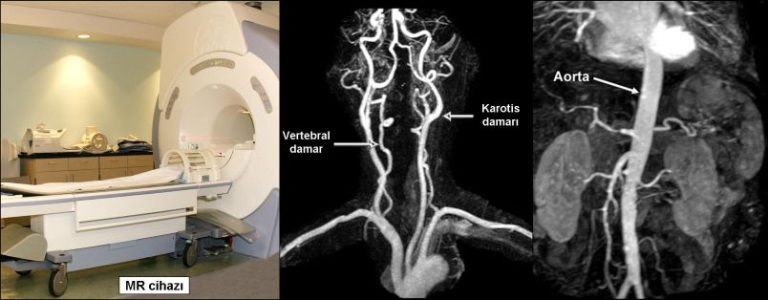

MR anjiografide, hasta tüp şeklinde büyük bir mıknatısın içine yatırılarak manyetik alan ve radyo dalgalarından yararlanılarak damarlar görüntülenir. Hastaya hiç ilaç vermeden bile damarlar görüntülenebilir, ancak son yıllarda kol toplardamarından ilaç verilmesi tercih edilmektedir. MR ile vücuttaki tüm damarlar görüntülenebilir. Özellikle ultrasonografinin iyi gösteremediği beyin, göğüs ve karın bölgesindeki damarlar da çok iyi incelenebilir. Ayrıca tüm damarlar üç boyutlu olarak istenilen açıdan değerlendirilebilir.

MR anjiografinin en önemli üstünlükleri vücuttaki tüm damarları hastaya radyasyon vermeksizin gösterebilmesidir. Günümüzde en çok beyin, boyun, bacak ve karın damarlarında kullanılır. En önemli dezavantajı vücudumuzdaki kalp, damar ve barsak gibi organların hareketleri nedeniyle “artefakt” adı verilen bazı yanıltıcı görüntülerin oluşmasıdır. Bu nedenle normal olan bazı damarları daralmış, daralmış bazı damarları da tam tıkalı gibi gösterebilir. Ayrıca damar duvarında kireçlenme ve vücutta bulunan metal parçaları görüntüyü bozabilir. Bazı durumlarda da atardamar ve toplardamarlar birbirlerinden ayrılamayabilirler. Bu yüzden MR anjiografi tıpkı renkli Doppler ultrasonografi gibi damar hastalıklarının görüntülenmesinde bir “ön test” olarak kullanılır. Bu ön testlerde bir anormallik saptanırsa genellikle BT anjiografi ve klasik anjiografi gibi yöntemlerle ileri inceleme yapılır.

BT anjiografide de hasta tekerlek şeklinde bir cihazın içine yatırılarak önce kol toplardamarından damarları boyayan bir ilaç verilir. Daha sonra hızlı bir şekilde vücudun incelenecek kısmından kesit şeklinde çok sayıda tomografi görüntüleri alınır. Bu ince kesitler bilgisayar ortamında birleştirildikten sonra da üç boyutlu anjiografi görüntüleri elde edilir.

BT anjiografide de tıpkı MR anjiografide olduğu gibi vücuttaki tüm damarlar incelenebilir. Özellikle koroner kalp damarlarının incelenmesinde günümüzde klasik kalp anjiosuna alternatif bir yöntem haline gelmiştir. Ayrıca karın, beyin ve boyun damarlarının görüntülenmesinde de birçok durumda klasik periferik anjiografinin yerini almıştır. Görüntüler MR’ a göre daha net olduğundan ve hareket artefaktlarından daha az etkilendiğinden, BT anjiografi görüntüleri MR anjiografiye göre daha kaliteli ve güvenilirdir. Ancak BT anjiografide hasta radyasyon alır ve mutlaka damardan ilaç (kontrast madde) vermek gerekir. Bu ilaç özellikle böbrek yetmezliği olan hastalarda dikkatli kullanılmalıdır. Ayrıca her incelemede sınırlı bir alan taranabilir. Bu özellikleriyle BT anjiografi genellikle klasik anjiografi yapmadan önce uygulanan ve bazı hastalarda klasik anjiografinin yerini tutabilen bir yöntemdir. En önemli üstünlüğü sadece damarın içini değil damar duvarını da gösterebilmesi ve duvar içinde yer alan kan, pıhtı ya da henüz damarda belirgin tıkanma yaratmayan ateroskleroz gibi patolojileri de gösterebilmesidir.